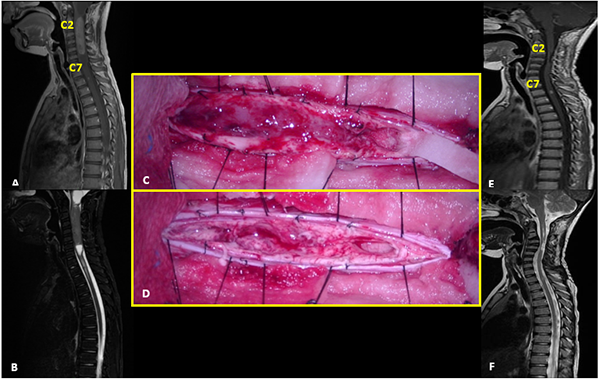

Figura 5:

Ependimoma. A-B: RM prequirúrgica T1 con contraste y T2 cortes sagitales. C-D: Imágenes intraoperatoria pre y postresección. E-F: RM postquirúrgica T1 con contraste y T2 cortes sagitales.